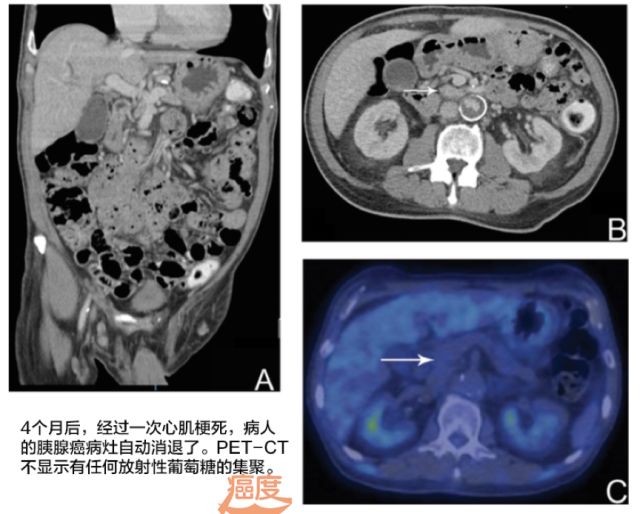

距离最初确诊为胰腺癌的4个月之后,再次影像学检查发现之前肝内胆管和胆总管胆道扩张已经解决。而且之前的胰头癌病灶几乎已经看不见了。真是奇怪了,为了避免万一患者做了高大上的PET-CT,这次结果再次验证了奇迹真的发生了,胰腺部位没有任何放射性葡萄糖的聚集。